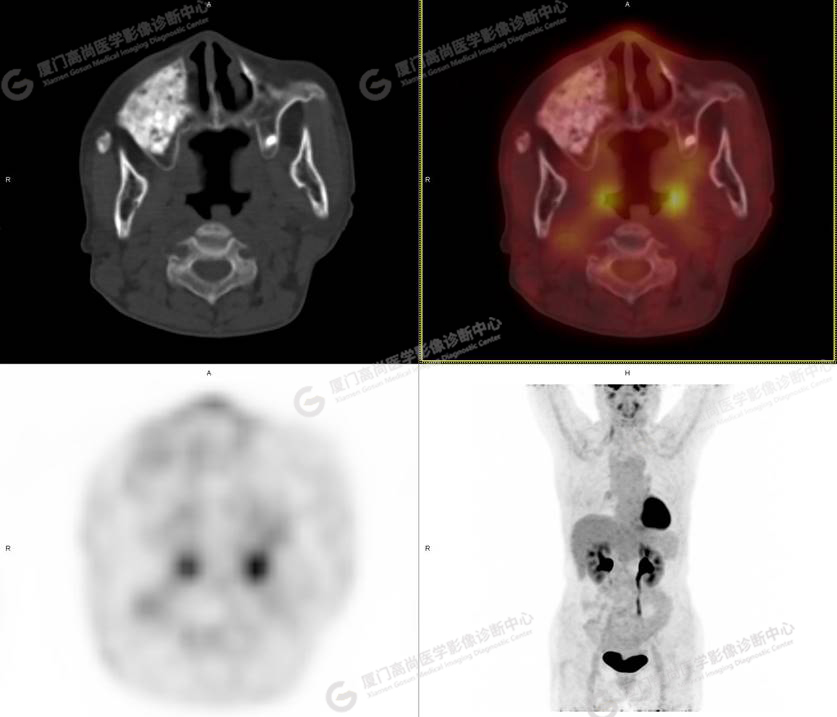

圖1

圖2

PET/CT所見:右側(cè)上頜骨、右側(cè)顴骨及右側(cè)額骨骨質(zhì)膨脹,其內(nèi)密度不均勻性增高,部分放射性攝取輕微增高,SUVmax 2.27。